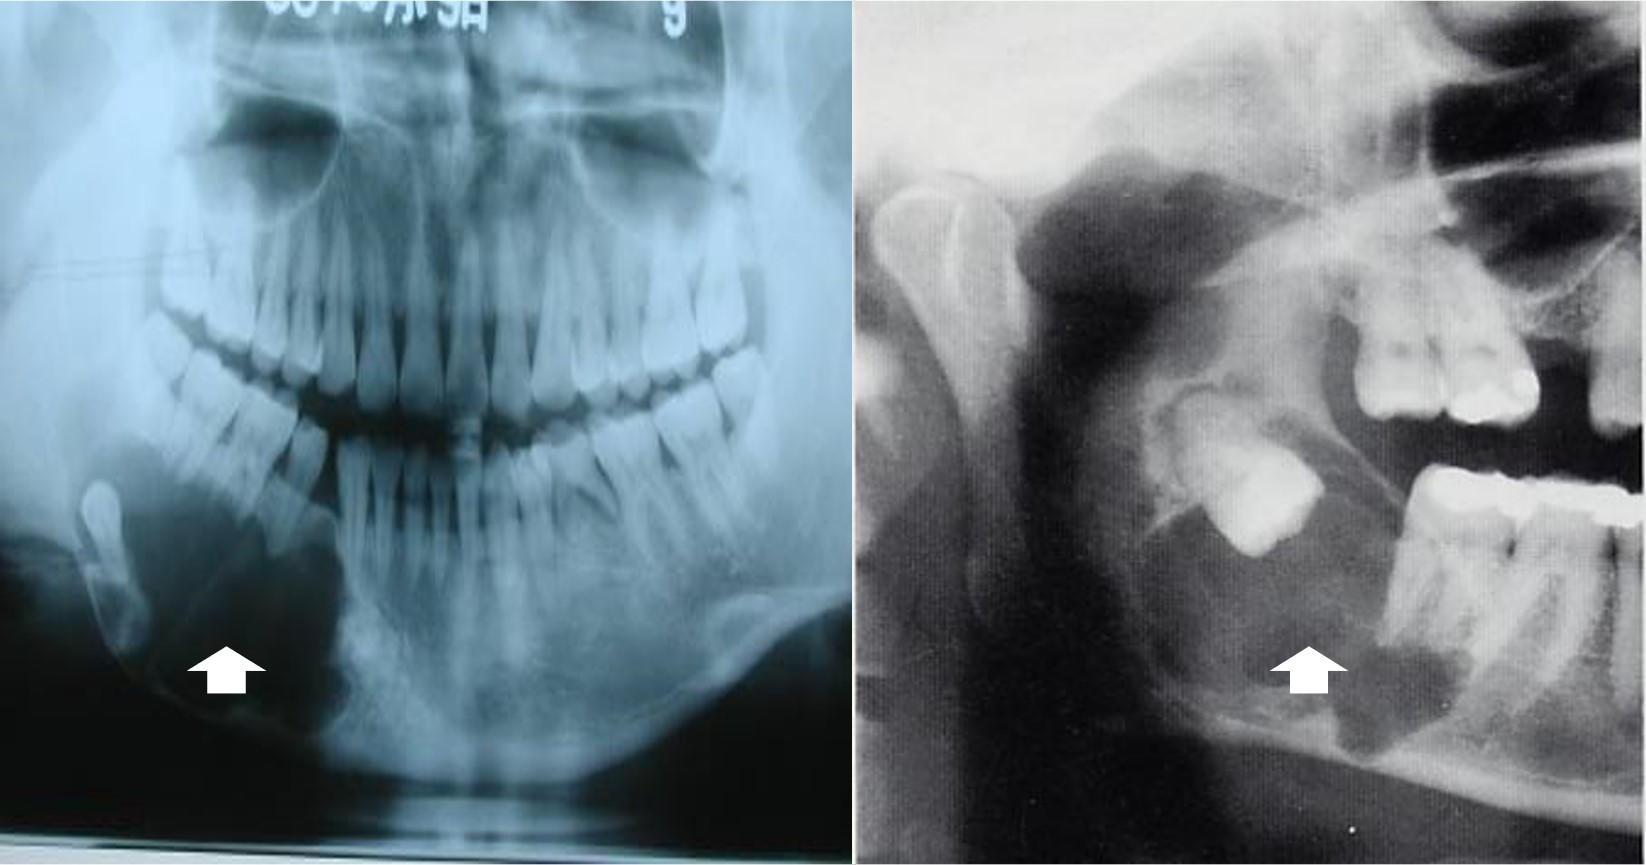

多见于10-29岁,男性多见,最常累及下颌骨磨牙及升支部,多为单发,其生长方式特殊,主要沿颌骨前后方向生长,因此多数患者无明显症状,有症状者主要表现为颌骨膨大,继发感染可出现疼痛、瘘管形成等。X线表现单房或多房性透光区,边缘有扇形切迹(图13.1-4),但总体上其X线表现多样,缺乏特异性,需要组织病理学诊断。

图13.1-4 牙源性角化囊肿(X线)